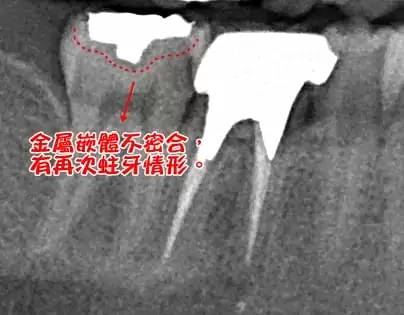

(圖一)

X光片顯示(圖一),大面積金屬嵌體補綴下,還有再次蛀牙的情形,患者因為美觀的考量,想要將金屬嵌體換掉,對於患者咬合大面積的補綴,又有再次蛀牙情形,所以初步建議患者在去除金屬嵌體及蛀牙面積後,在沒有影響到牙髓腔(牙神經)的狀況下,做CEREC 3D齒雕全瓷補綴,既能達到美觀的呈現,又能恢復牙齒的健康。